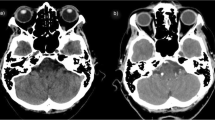

There are several limitations to our study. First, RT techniques including two-dimensional RT, three-dimensional conformal RT or intensity modulated radiation therapy (IMRT) cannot be differentiated by using the NHIRD. Moreover, each patient may receive different radiation dose. However, total dose of 66–74 Gy in 1.8–2.12 Gy per fraction were usually prescribed for head and neck patients with gross tumor and total dose of 60–66 Gy in 1.8–2 Gy per fraction were usually prescribed for head and neck patients in adjuvant treatments. Therefore, the total radiation dose differences between NPC-RT and non-NPC-RT groups were limited. Consequently, we were able to compare the effect of radiation based only on the different radiation fields between these two groups. Next, we were unable to retrieve imaging data. Unlike general aneurysms, radiation-induced intracranial aneurysms can originate from the arterial wall rather than a branching site [13]. This uncommon location may be related to vessel wall degradation caused by radiation [24]. In addition to aneurysm location, the shape of an aneurysm may also be affected by RT. Radiation-induced intracranial aneurysms are more likely to be fusiform or pseudoaneurysms [40]. Because no detailed imaging data are included in the NHIRD, it was unable to confirm the locations and shapes of aneurysms in this study. Cahan et al. [53] mentioned that radiation-induced tumors should be located within the radiation field and that they should not present before radiation. While the systemic effects of radiation should be considered, detailed imaging reports are required to improve diagnostic accuracy. Finally, other risk factors of developing aneurysms formation including smoking, alcohol abuse and family history of intracranial aneurysms were not recorded in NHIRD [51, 54, 55]. It was unable to analyze the confounding effect of these well-known risk factors. Because of these limitations, more studies were needed to determine the diagnostic criteria of radiation-induced intracranial aneurysms.